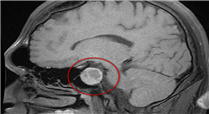

垂体瘤的诊断通常结合临床表现、影像学检查与激素水平检测。其中,影像学检查有助于明确肿瘤大小与位置,血液激素检测则可帮助判断肿瘤是否具备分泌功能。